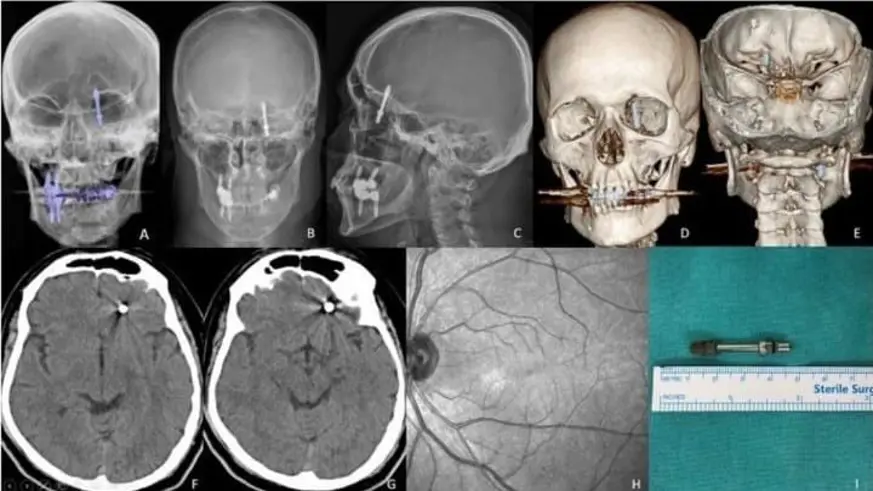

İddiaya göre; tedavi sırasında çene kemiğini delen diş, Yılmaz'ın kafatasına saplandı.

Yılmaz, acılar içinde baygınlık geçirirken Doktor A.D. röntgen çekerek vidanın beyne saplandığını tespit etti ve hastasını özel aracıyla hastaneye bıraktı.

Hastanede çekilen tomografi sonrası gözlerine inanamayan doktorlar, 2 çocuk babası adamı hemen ameliyata aldılar.

Kendisini uyarmasına rağmen dinlemediğini ifade eden Yılmaz, "Daha sonra dişlerimi çekip, aynı gün implant uygulaması yaparken, işlemde kullandığı cihazın bozuk olduğunu sekreterine söyledi. Bu kez de işlemi eliyle yapmaya başladı. Vidayı yerleştirmeye çalışırken, aşırı yüklendiğini fark ettim. Bunu kendisine söyledim, kemik sesi geldiğini ifade ettim. Fakat bu kez de bana bunun normal olduğunu söyledi. Ama vidayı zorlarken, vida çene kemiğimi delip göz duvarının arkasından beyin omurilik sıvısının olduğu bölgeye saplandı. Ben acıdan dolayı bağırınca röntgen çektirdi" dedi.

Doktorun kendisini hastaneye bırakıp kaçtığını iddia eden Yılmaz, "Durumun ciddiyetini anlayınca beni Uludağ Üniversitesi Hastanesinin Acil bölümüne getirip gitti. Burada yapılan inceleme sonrası vidanın beyin omurilik sıvısının olduğu yere saplandığı görüldü. Daha sonra uzman hekimler bir araya gelip, ameliyat için karar aldılar. Ameliyat öncesi bana hayatımı kaybedebileceğimi söylediler. Ben artık çocuklarımla helalleşip vedalaştım. Çok şükür ameliyattan sağ salim çıktım. Bu süreçlerde diş hekimi hiç bir zaman yanımda olup mağduriyetimi gidermedi, hatta ödediğim ücreti dahi geri iade etmedi. Üstüne üstelik benimle dalga geçer gibi konuştu. Bunların hepsi belgeli. Ben yetkililerden devlet büyüklerimizden bu konuyla ilgilenilmesini istiyorum. Benim iki çocuğum var. Bana bir şey olsaydı bunların hesabını kim verecekti ? Şimdi dava sürecine girdik. Kendisinden şikayetçi oldum" diye konuştu.

Yılmaz'ı sağlığına kavuşturan doktorların başarılı ameliyatı, Amerika'da literatüre girip dergilere konu oldu